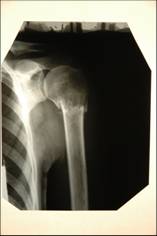

Андрей

После лечения:

Андрей после лечения

До лечения:

Андрей до лечения